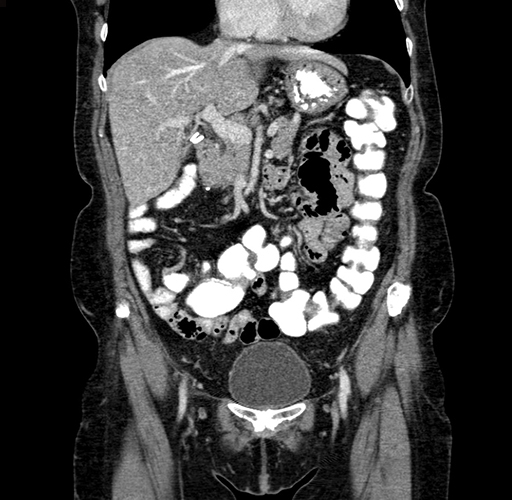

Pre-Chemo: Coronal Venous

Coronal Venous